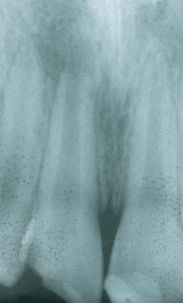

El diente fue tratado endodónticamente con apexificación utilizando hidróxido de calcio y luego se rellenó con gutapercha. Observe el gran espacio del canal y la delgada estructura interior del diente.

El diente fue restaurado como se ha descrito anteriormente, se grabó el canal radicular, se colocó adhesivo y un composite híbrido dual. Para este caso se utilizaron dos piezas de Ribbond de 3 mm que se colocaron en la resina usando un instrumento para endodoncia de Ribbond.

2 piezas de Ribbond de 3mm

colocadas dentro del canal

Debido a que el paciente era un joven adolescente la restauración final fue una Clase IV de composite. En la radiografía se ve como la fibra Ribbond se ha unido al composite.